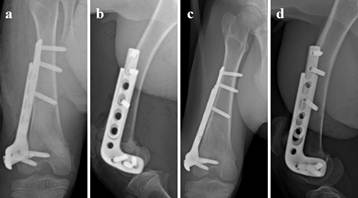

Radiographic analysis of the femurs in the goats revealed that the sliding plate group could be extended as the femur grew. The epiphyseal morphology in the sliding plate group was kept essential normal. However, the phenomenon of the epiphyseal growth retardation and premature closure were very common in the regular plate group (Fig. 2 and Fig. 3).

Fig 2

Experimental goat distal femur was fixed with sliding plate. The sliding plate extended accordingly as the epiphyseal plate grows. a: Posterior-anterior radiograph of goat femur (postoperative 0 day). b: Lateral radiograph of goat femur (postoperative 0 day). c: Posterior-anterior radiograph of goat femur (postoperative 4 weeks). d: Lateral radiograph of goat femur (postoperative 4 weeks).

Experimental goat distal femur was fixed with regular plate. The plate and screws restricted the epiphyseal unequal growth. a: Posterior-anterior radiograph of goat femur (postoperative 0 day). b: Posterior-anterior radiograph of goat femur (postoperative 4 weeks).